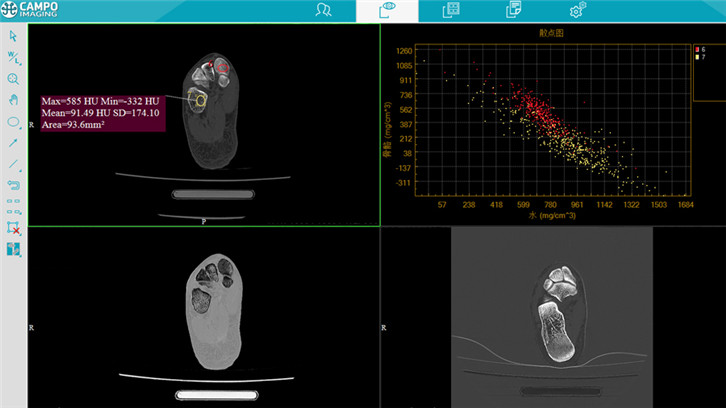

能谱显示

达峰分析